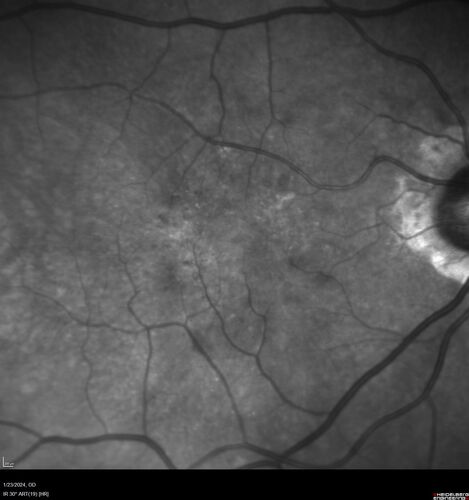

wet AMD with classic extrafoveal macular neovascularization in the good eye

89 year old man with longstanding vision loss in the left eye presented with one month of mild vision loss in the right eye.  Vision was 20/32.  This eye responded to vabysmo therapy.